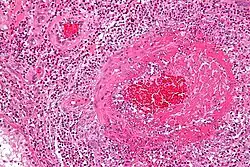

Pathologie

Feingeweblich zeigt sich eine starke Vermehrung eosinophiler Granulozyten im Gewebe (Gewebseosinophilie), mit Befall vor allem der kleinen Blutgefäße (mit Zerstörung, Blutgerinnselbildung und daraus resultierenden Infarkten). Daneben kann die Entzündung auch direkt auf verschiedene Organe übergreifen, z. B. auf das Herz mit der Folge einer eosinophilen Herzmuskelentzündung.